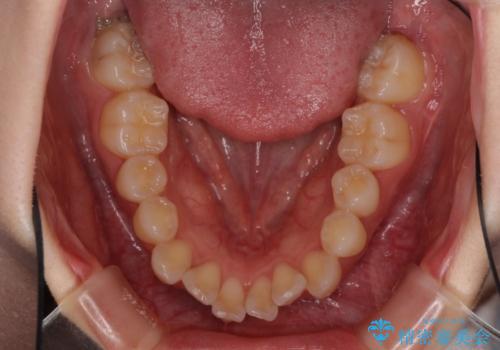

前歯のデコボコと突出感 インビザラインで改善

- 上下前歯のデコボコを気にして来院された患者様です。

インビザラインによる上下歯列の側方拡大と後方移動、IPR(歯と歯の間を削る)にるスペースの獲得により歯列を整えることとしました。